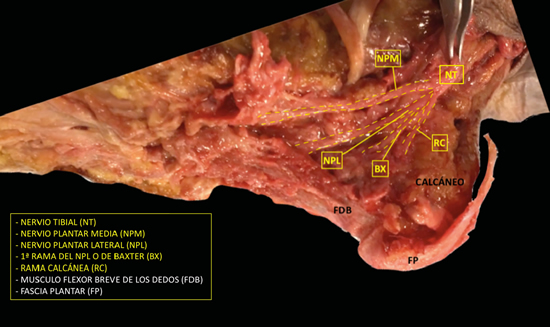

Figura 2. Imagen de disección del nervio tibial y sus ramas.

El nervio tibial, en su tránsito por la cara medial del tobillo y del pie, dará las ramas calcáneas mediales, el nervio plantar medial, el nervio plantar lateral y la primera rama del nervio plantar lateral o rama de Baxter3. El nervio peroneo profundo se localiza en profundidad a la musculatura extensora del primer radio a la altura del tobillo. El nervio peroneo superficial discurre por el borde anterior del peroné para llegar escindido al tobillo en los nervios cutáneo dorsal medial y cutáneo dorsal intermedio. El nervio sural, situado en el aspecto posteromedial de la pierna adyacente a la vena safena menor, dará las ramas calcáneas laterales antes de girar retromaleolar al peroné hacia el pie para denominarse como el nervio cutáneo dorsal lateral (Figuras 2 y 3)2,3.